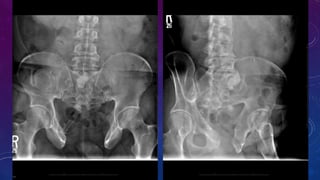

WHAT DISEASE? WHICH IS ABNORMAL ORGAN?

Associated bony findings include widely separated pubic bones with absent symphysis pubis

leading to characteristic " waddling gait". This appearance on AP plain radiograph of the pelvis has

been likened to a manta ray swimming towards you (manta ray sign).